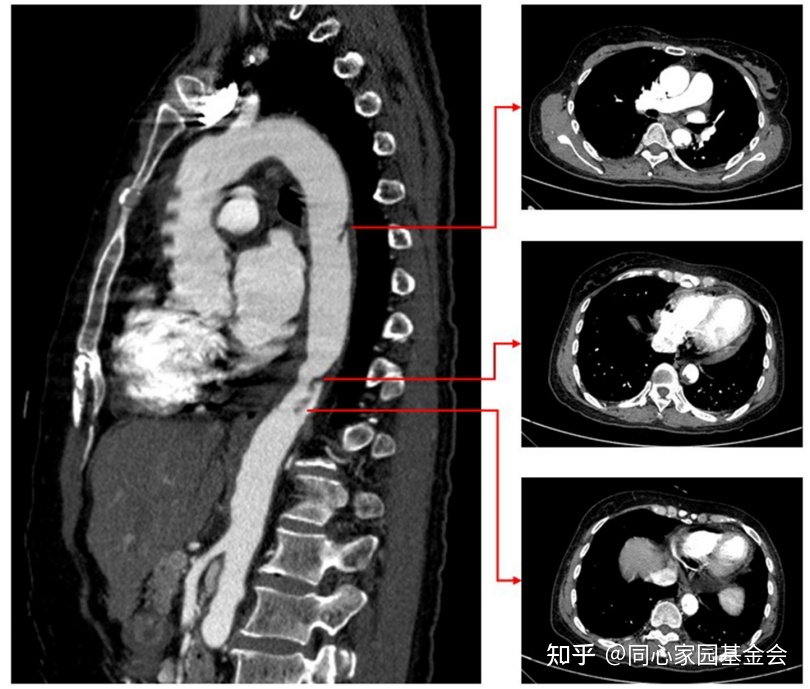

抗凝治疗10天后,CTA复查显示主动脉壁血栓明显变小(图4)。

图4:复查CTA 显示主动脉壁血栓显著变小。

血小板计数为299 × 10^9/L,肌钙蛋白 I 为0.032 ng/ml,D-二聚体为0.25 μg/ml。

由于血栓形成最重要的实验室指D-二聚体已经降到正常范围,认为血栓已经溶解。但是由于经济原因,患者拒绝再次进行CTA检查。